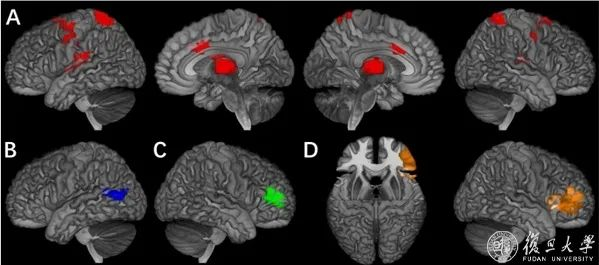

类脑研究院贾天野课题组发现青少年多动及注意力缺陷等外向障碍在多个认知环路上的调控机制

图示:A)奖赏预期下的多动行为核心脑区;B)行为抑制任务下的冲动行为核心脑区;C)行为抑制任务下的注意力缺陷核心脑区;D)行为抑制任务下的品行问题的核心脑区

近日,复旦大学类脑智能科学与技术研究院青年研究员贾天野与英国伦敦国王学院、复旦大学特聘讲座教授冈特·舒曼(Gunter Schumann)共同领衔的国际团队,首次系统性地从多个特异性的认知环路分析了青少年精神和行为障碍的认知调控机制,并找到了外向障碍相关特征行为在不同认知领域特异性的功能脑区。研究者进一步从神经影像层面对这些高度关联的特征行为进行分型,发现注意力缺陷障碍和品行障碍由行为抑制任务下的右侧下额叶区域共同调控,揭示了两者共病的脑网络机制。

4月20日,相关研究成果以《强化相关行为的神经行为学特征及分型研究》为题发表在自然杂志子刊《自然-人类行为》(Nature Human Behaviour),该研究不仅揭示了外向障碍共病及分型的认知环路调控机制,同时为跨疾病诊断及分型治疗提供了重要的理论基础。